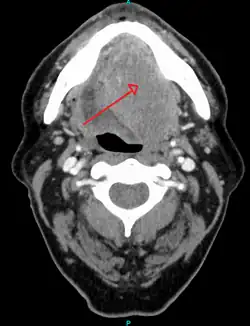

Head and neck cancer

About 90%[4] of cases of head and neck cancer (cancer of the mouth, nasal cavity, nasopharynx, throat and associated structures) are due to SCC.